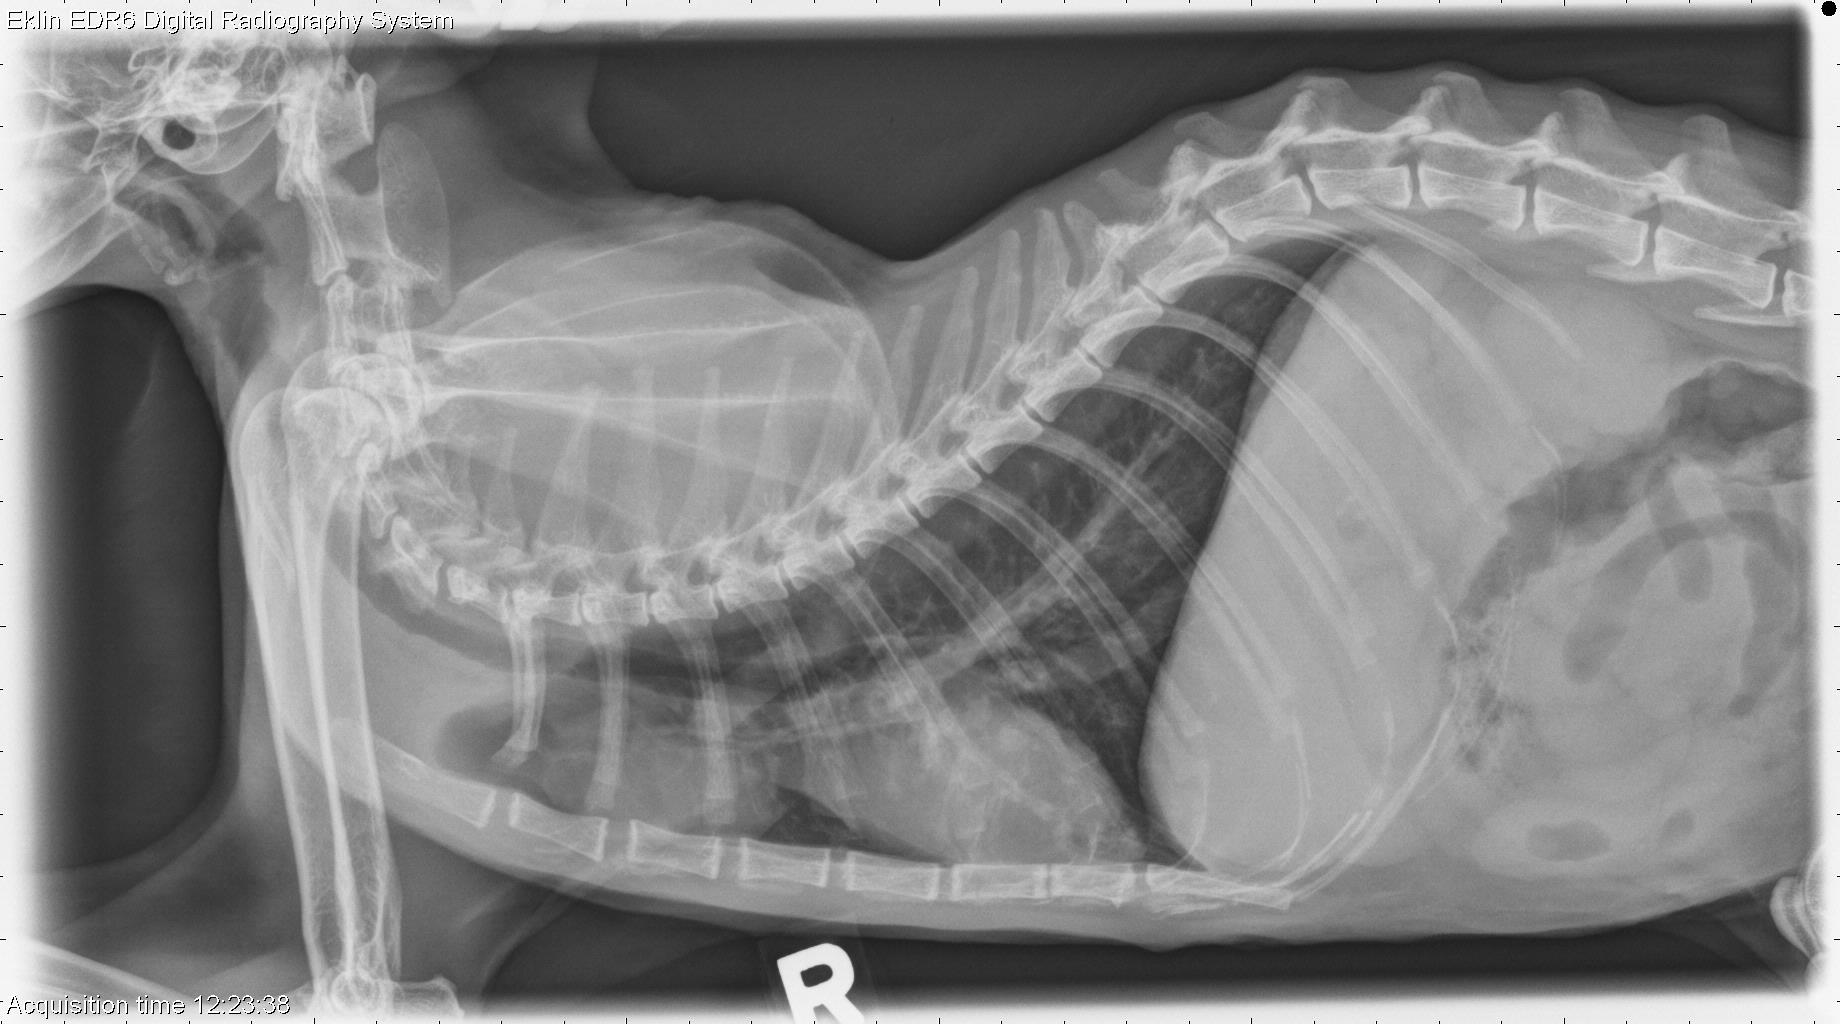

Normal Cat Thoracic Radiographs Thymus In Cats Thymoma is a rare neoplasm seen in aged cats that derives from thymic epithelial cells and is usually located in the cranial mediastinum. Thymoma is an uncommon (17/3284 feline neoplasms in one study) tumor. As a cat ages the thymus is no longer needed because other parts of the body take over the job of fighting infections. Thymoma occurs in. Thymus In Cats.